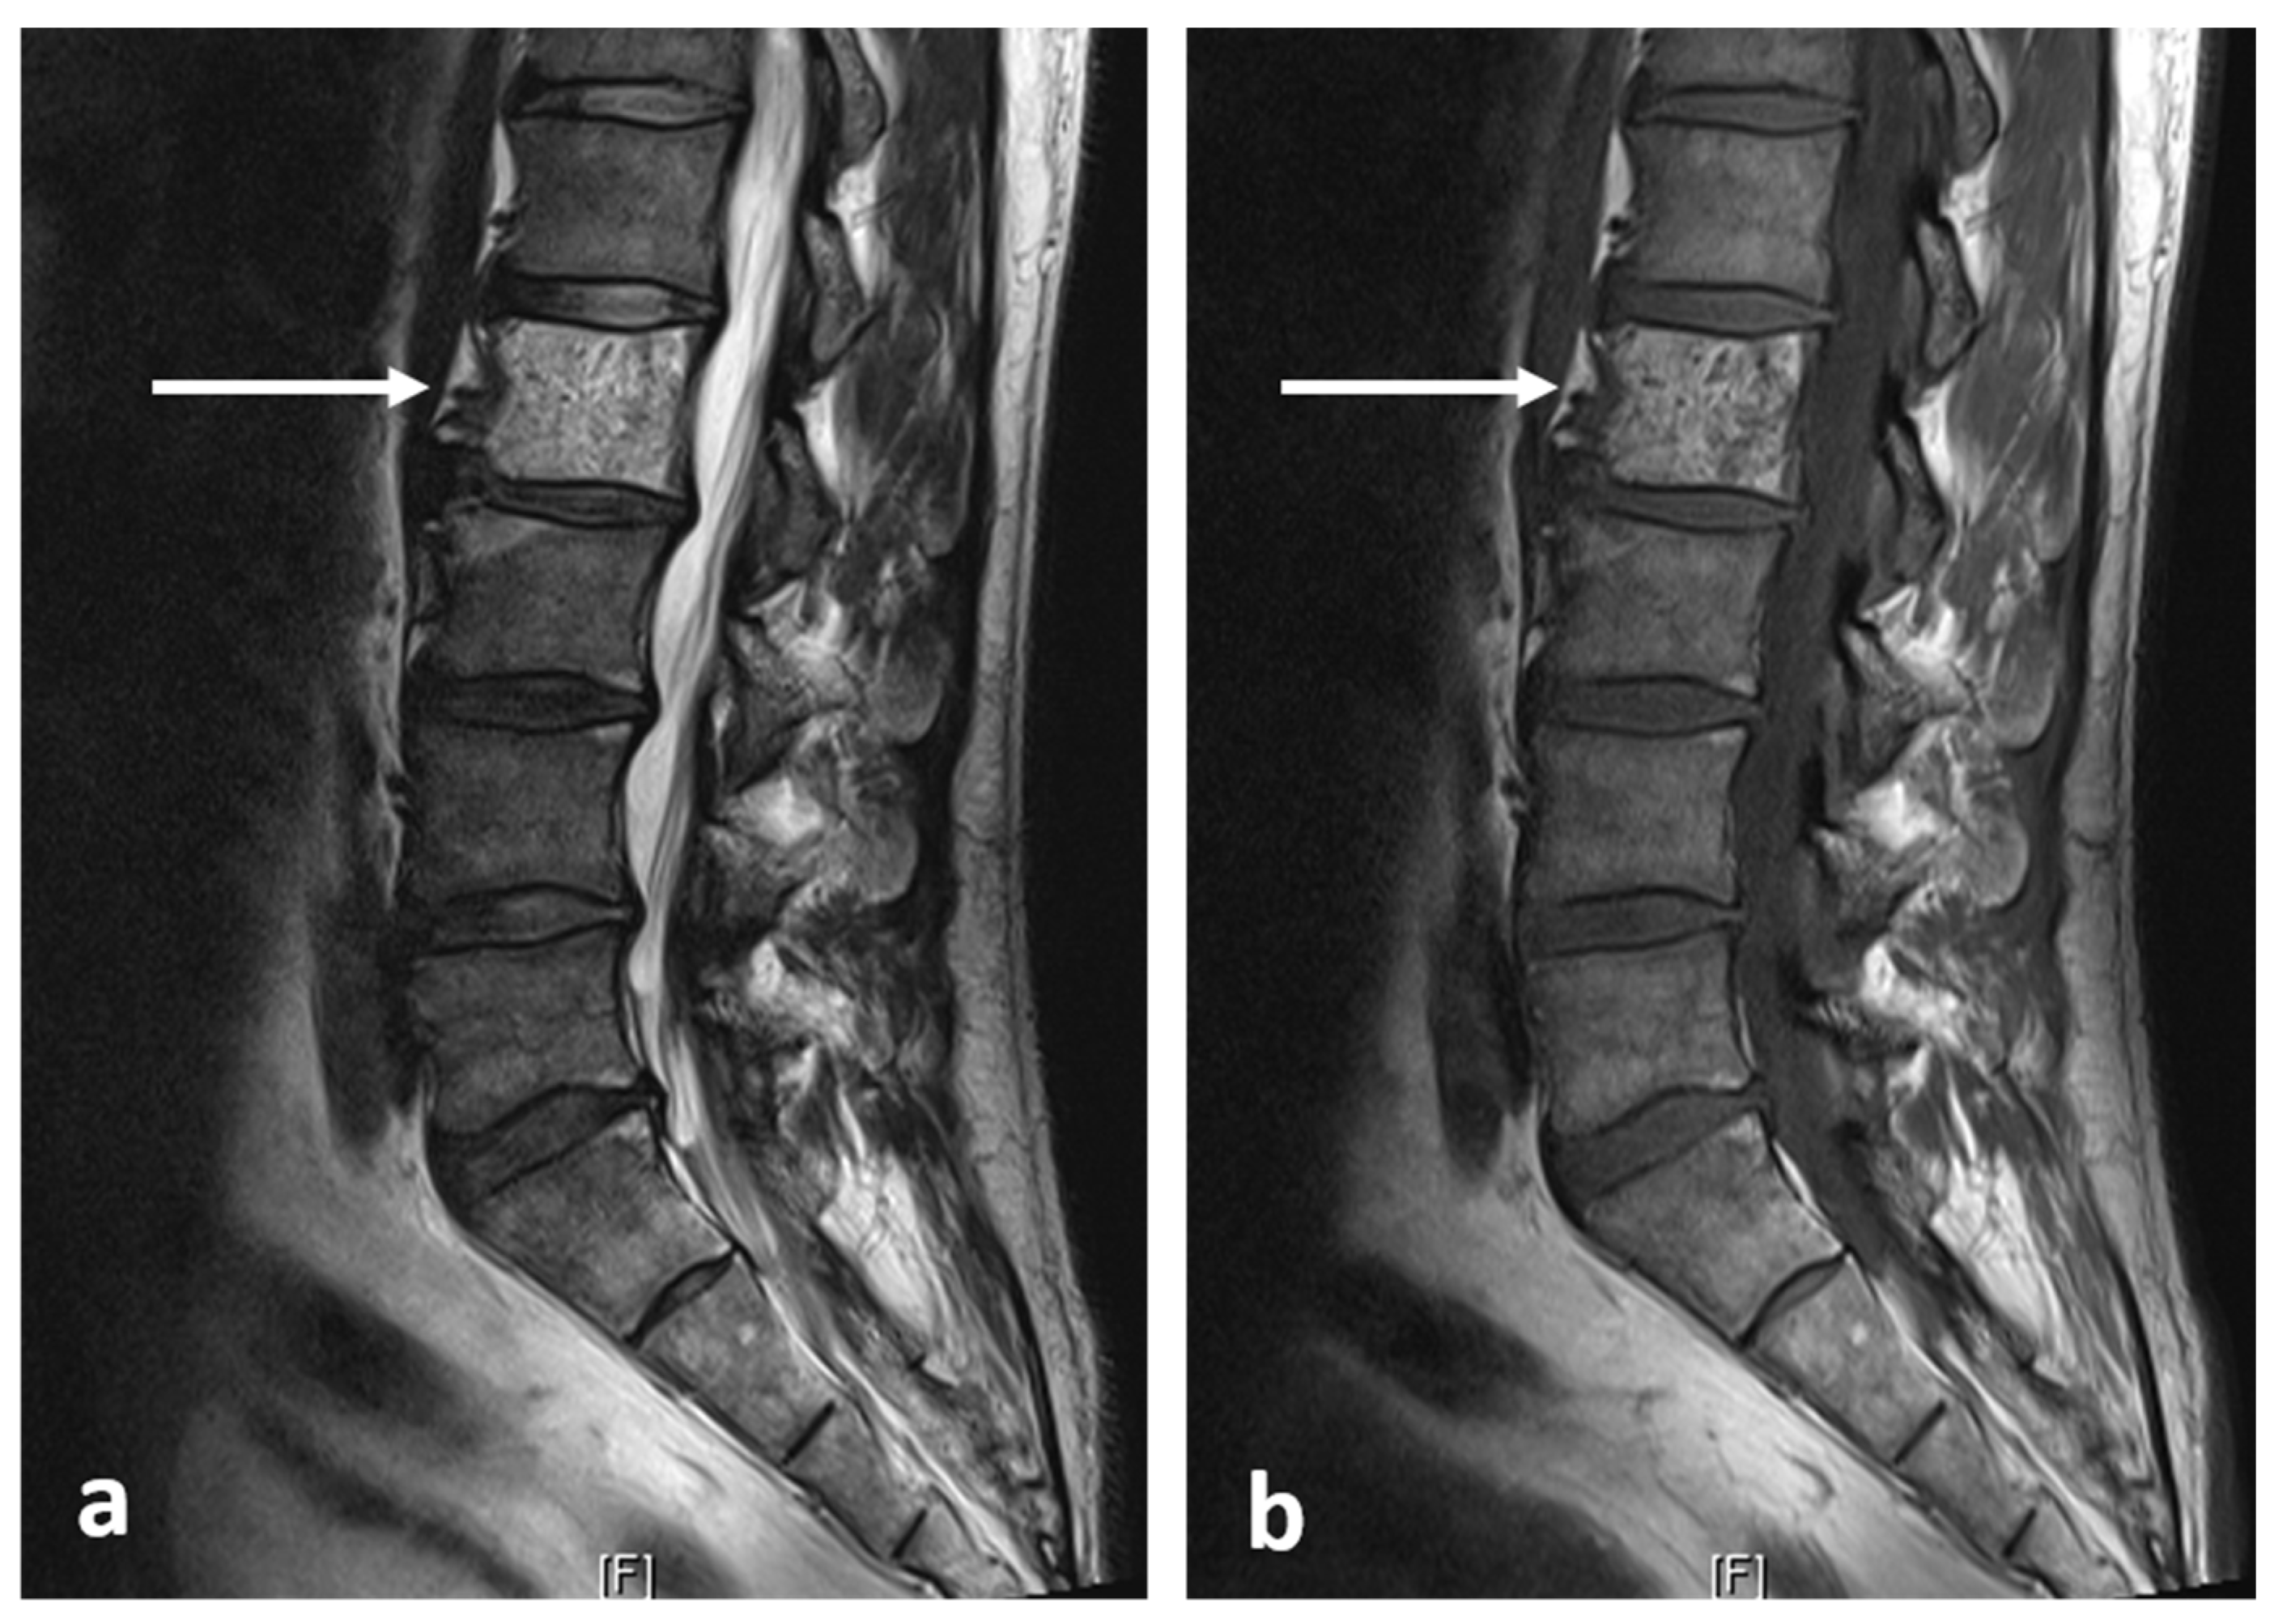

| Aneurysmal bone cyst | Expansile lytic lesion with internal bone septations. | Fluid—fluid levels within the cysts, high T1 signal within layering fluid content due to haemorrhage. |